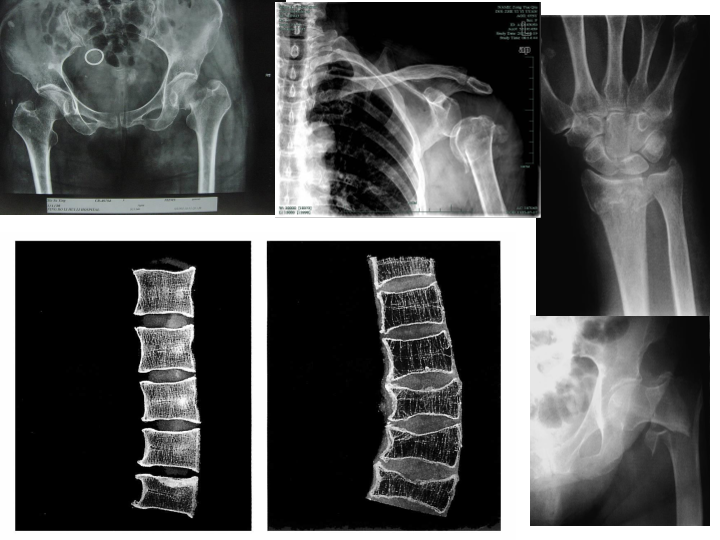

骨质疏松症的诊断和治疗